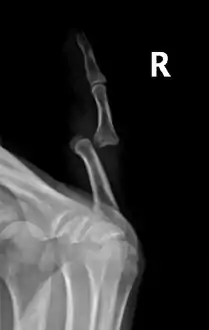

- Finger: Interphalangeal (IP) or metacarpophalangeal (MCP) joint dislocations[31]

Dislocation of the left index finger

Radiograph of right fifth phalanx bone dislocation

Radiograph of left index finger dislocation

Radiograph of right fifth phalanx dislocation resulting from bicycle accident